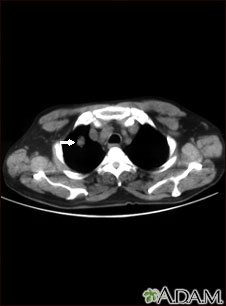

- To look for blood clots in the lungs

- Other abnormal changes of the major blood vessels in the lungs or chest such as blood clots (pulmonary embolism)